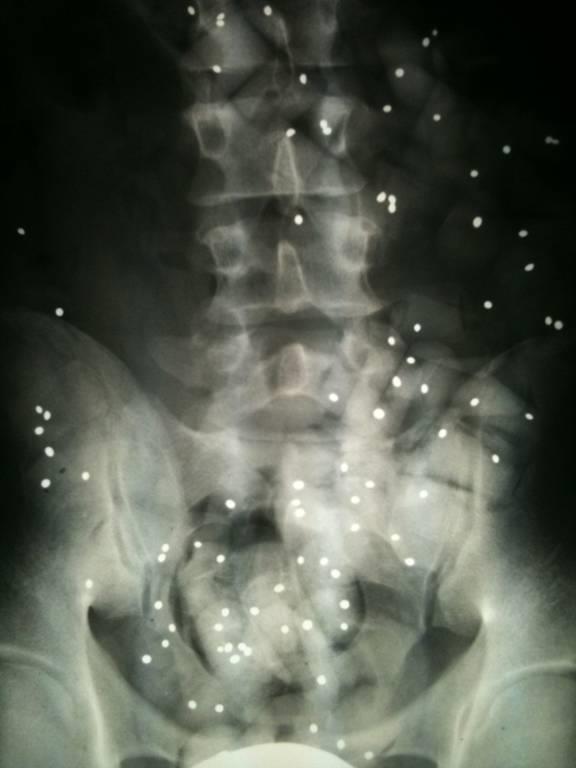

Wie wichtig sind Röntgenbilder?

Röntgenbilder sind wichtig, aber häufig überbewertet.

Wenn keine Hinweise auf eine scherwiegende Erkrankung (spezifische Rückenschmerzen) vorliegen dann ist die genaue Befragung und die Untersuchung wichtiger als Röntgenbilder.

Wenn Sie Röntgenbilder mitgebracht haben werden wir und diese gemeinsam mit Ihnen anschauen.

Nicht selten erwidern Patienten auf die Frage, was sie zu uns führt, mit der Antwort: "Schauen sie die Bilder an, ich habe 3 Bandscheibenvorfälle!".

3 relevante Vorfälle sind selten und solche Aussagen kommen zustande, wenn die Röntgenbefunde fehlinterpretiert werden.

Lesen Sie folgenden Kernspinbefund und Sie sind überzeugt so richtig krank zu sein:

Der Befund kann für einen durchschnittlichen 50jährigen durch 2 Worte ersetzt werden:

Altersentsprechender Befund.

Der Radiologe beschreibt auf den Bildern alles was er sieht, und das sind natürlich auch Verschleißerscheinungen.

Wenn ein Gutachter mein Auto (150.000km) beurteilt, wird ein mehrseitiger Bericht dabei herauskommen. Dass ich aber damit dennoch im Jahr problemlos 30.000km fahre ist davon unbenommen.

Verschleiß ist normal; meistens macht das keine Probleme.

Bei jeder Bewertung eines Befundes ist die Relevanz wichtig. Darum werde ich die Röntgenbilder mit Ihnen besprechen.

Mache ich nur genügend Untersuchungen finde ich immer einen vielleicht behandlungsbedüftigen Befund. Das führt zu der Aussage, dass nur der gesund ist, der nicht ausreichend diagnostiziert wurde. Etwas zynisch, ist aber etwas wahres dran.